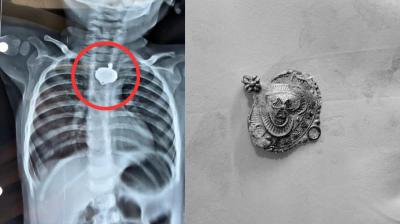

बड़वानी में 9 माह के बच्चे की आहार नली में फंसा मंगलसूत्र, डेढ़ महीने बाद एक्स-रे से खुलासा

24 Nov, 2025 08:30 AM IST | DIGIANANEWS.COM

बड़वानी: रविवार को जिला अस्पताल में एक बेहद संवेदनशील और हैरान करने वाला मामला सामने आया. जब 9 माह के एक बच्चे के गले में मंगलसूत्र फंसा हुआ देखा गया. घटना...